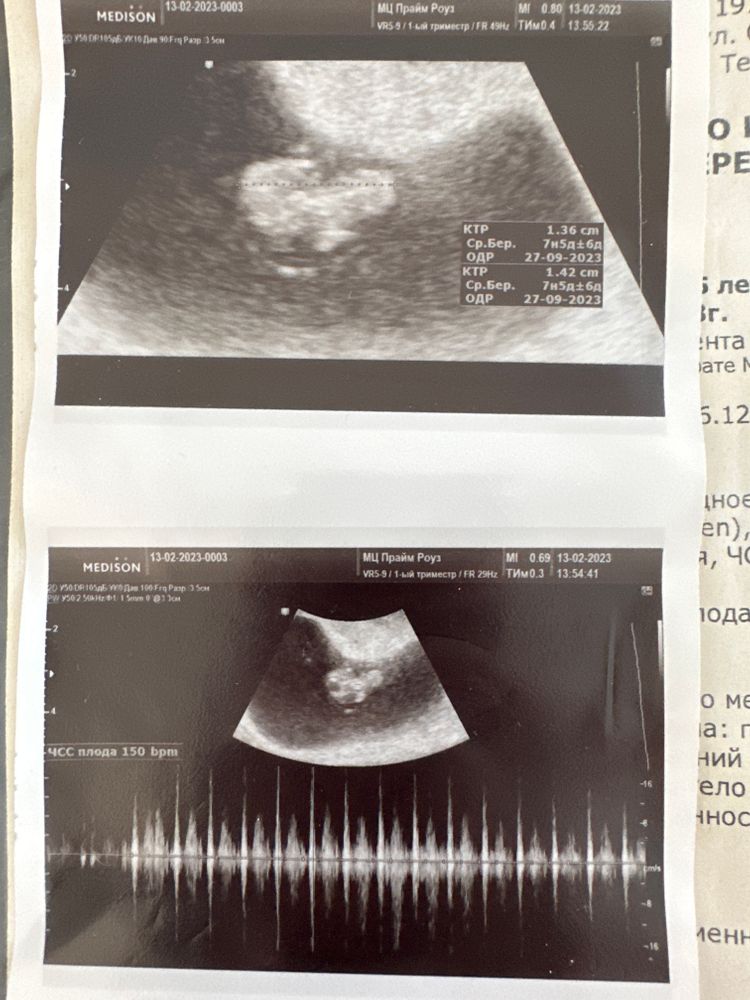

Растет бусинка) сердце ускорилось до 150 ударов. Несмотря на какие-то непонятные коричневые выделения длительностью в один день и тянущие боли, у нас всё норм) а такое было два раза уже на 5 и 7 неделе. Сейчас всего-то 8 неделя, а сколько уже сделано узи и потрачено нервов! Всем добра и благополучия 🫶🏼